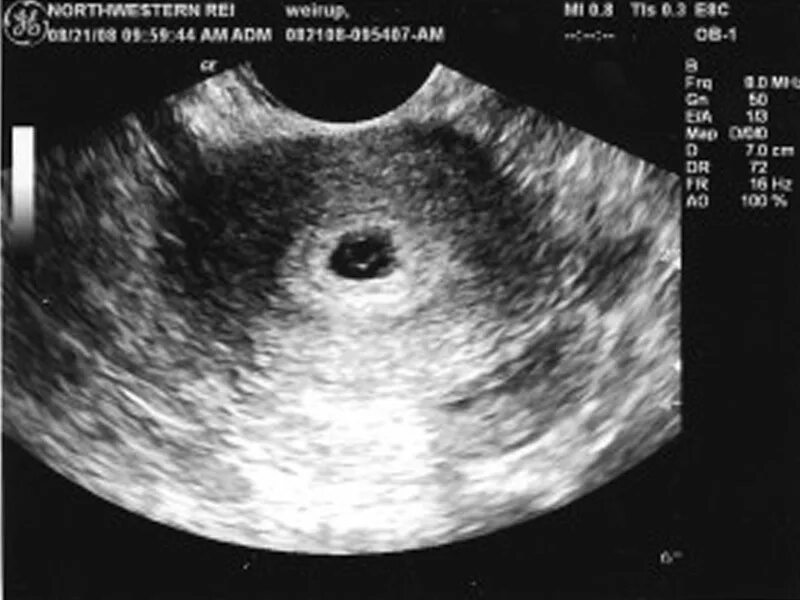

На каком сроке увидели плодное яйцо